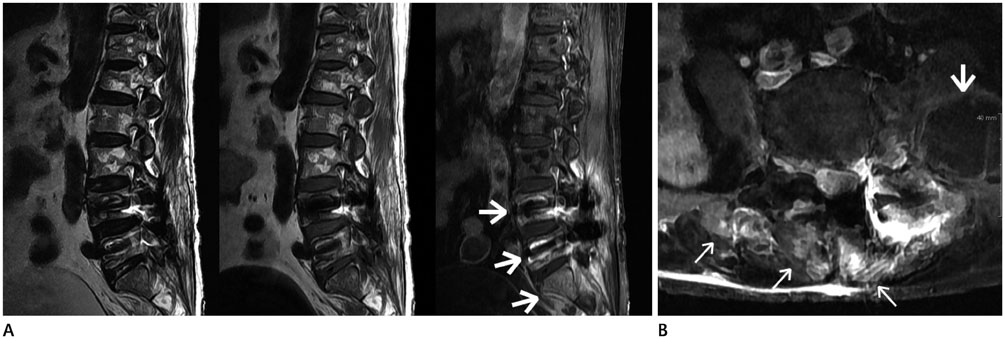

We retrospectively reviewed the clinical and MRI findings on 18 patients diagnosed with ISI. The MRI findings were evaluated for the number of spinal segments showing inflammation in the longitudinal span and affected vertebral bodies and discs, the presence of abscess in the epidural or paravertebral space, paravertebral myositis, and skip lesions.

Among the 18 patients, the range of the longitudinal span of spinal inflammation was 2-11 (mean = 5.84) vertebral segments. 17 of the 18 patients had three or more contiguous vertebral segments. The osteomyelitis and disc destruction was apparent in 77.8% and 66.7% of the patients, and 78% of patients with osteomyelitis showed involvement of one or two vertebrae; 91.7% of patients with disc destruction showed involvement of single disc. The incidence of epidural or paravertebral abscesses, and paravertebral myositis were 88.9%, and 94.4%. There were no spinal skip lesions.

MRI findings of those are wide longitudinal span of infection, involvement of no more than one or two vertebral bodies and a single disc, large abscesses, extensive myositis and no skip lesions, can be a useful ISI-diagnostic tool.